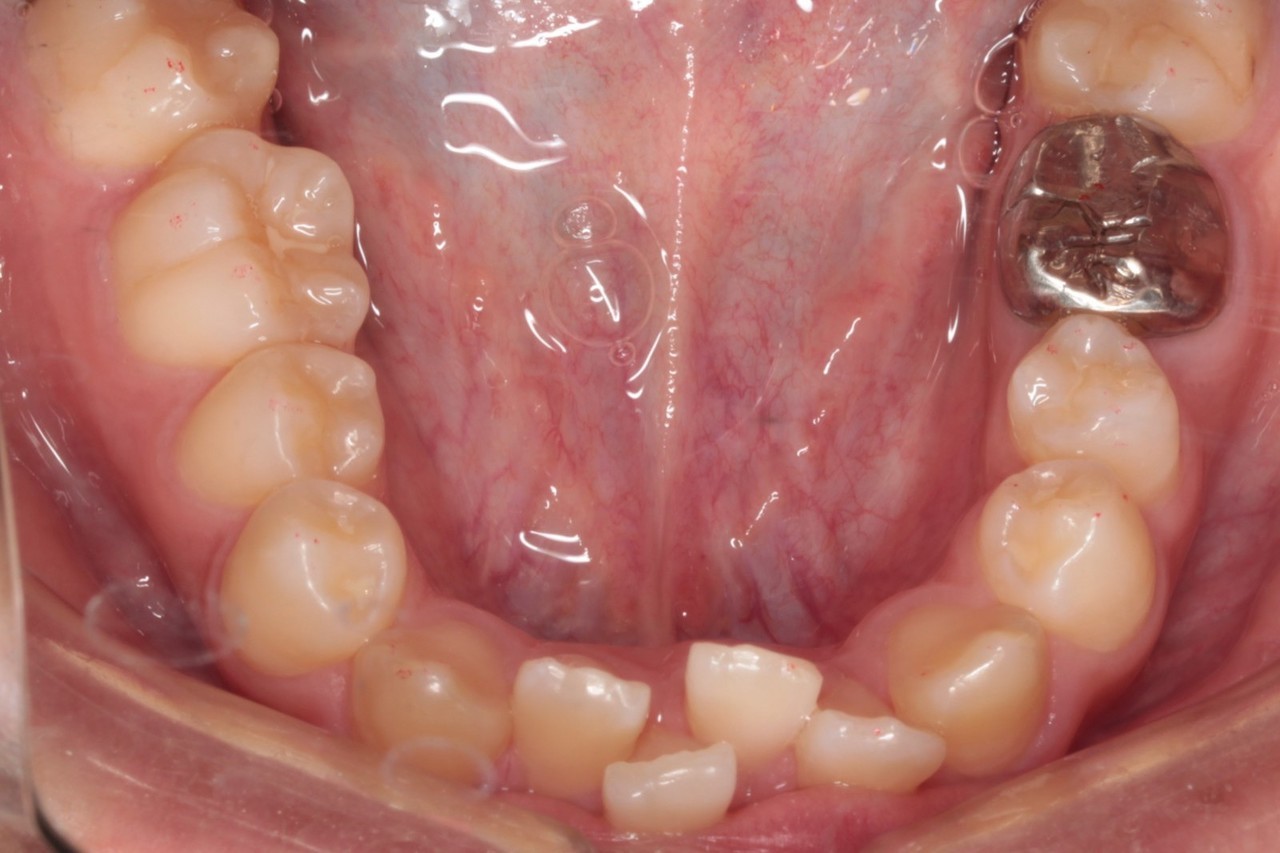

下顎 治療前

下顎 治療後